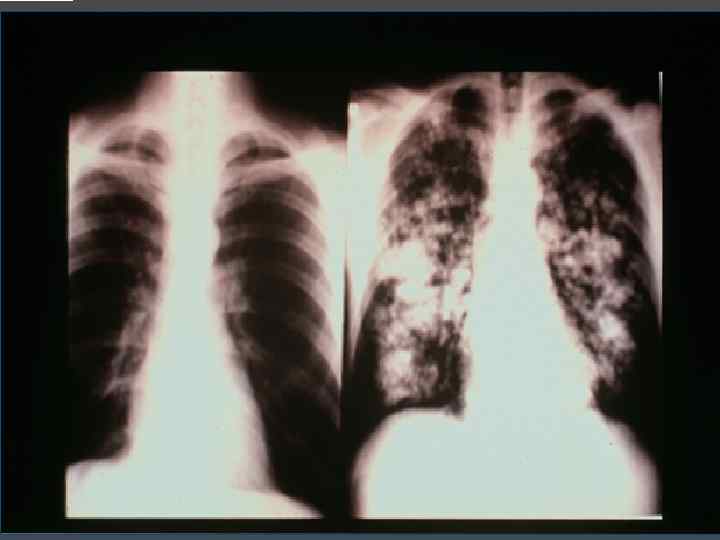

Метастатическая кальцификация мягких тканей, околосуставной кальциноз